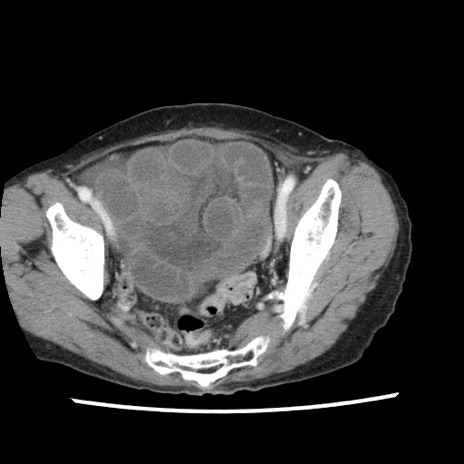

冠状断像